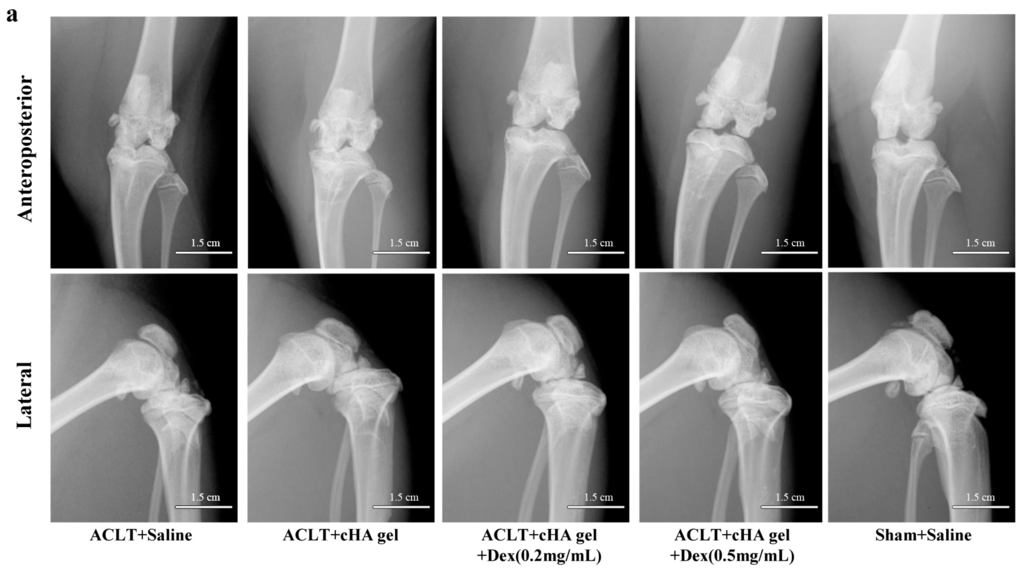

At 12 weeks after anterior cruciate ligament transection (ACLT), the knee joint space was significantly wider in the cHA-Dex (0.2 mg/mL) gel and cHA-Dex (0.5 mg/mL) gel groups, compared with the saline or cHA only groups (Figure 2a), indicating that intra-articular injection of the cHA-Dex gel exhibited preventative effects on OA. Radiographic osteophytosis grading system, which quantifies the severity of osteophytosis at the margins of the knee joint, showed that osteophytosis in the cHA gel only, cHA-Dex (0.2 mg/mL) gel and cHA-Dex (0.5 mg/mL) gel groups were significantly lower than that of saline group (p < 0.01). In addition, less osteophytes were found in the cHA-Dex (0.5 mg/mL) gel group compared with the cHA gel only group (p < 0.05) (Figure 2c).

Figure 2.

Intra-articular cross-linked hyaluronic acid-dexamethasone (cHA-Dex) hydrogel injection attenuated osteoarthritis (OA) macroscopically. Following anterior cruciate ligament transection (ACLT) surgical induction of OA, micro X-Ray (a) was used to evaluate the severity of OA in the right knee before the animals were euthanized; (b) Gross morphological cartilage lesion and fibrillation in the rat tibial plateau were visualized by Indian ink staining; (c) Radiographic osteophytosis was graded subjectively on a scale from 0 to 3 (0-normal, 1-mild, 2-moderate, 3-severe) based on the severity of osteophytosis at the margins of the knee joint; (d) Cartilage lesions and fibrillation was quantified using the Meachim grading system. Data were expressed as means ± SD. *, compared with ACLT + saline group, designated as * p < 0.05, ** p < 0.01 and *** p < 0.001; #, compared with ACLT + cHA gel group, designated as # p < 0.05, and ### p < 0.001.n = 10.

Micro X-ray and Indian ink staining revealed that both the cHA gel and the cHA-Dex gel intra-articular injections attenuated rat OA compared with the saline group. However, the cHA-Dex gel treatments exhibited greater relief from OA than the cHA gel only group. Histology and RT-qPCR data showed similar results. Both the cHA-Dex (0.2 mg/mL) gel and cHA-Dex (0.5 mg/mL) gel treatments reduced cartilage degradation. In Figure 6a, we noticed that aggrecan mRNA in cHA-Dex (0.5 mg/mL) is lower than that in cHA-Dex (0.2 mg/mL). However, in all other analyses, cHA-Dex (0.5 mg/mL) has same or higher effect than cHA-Dex (0.2 mg/mL). This discrepancy may be caused by epigenetic inheritance or variation of aggrecan and regulation of some unknown reasons after treatment with cHA-Dex in our study. We also noticed that the higher level mRNA of aggrecan in the cHA-Dex-treated animals compared with cHA treated animals alone. The result could be a combination effect from cHA-Dex chondroprotection with more aggrecan production, because the chondrocytes may try to produce more aggrecan to balance the loss of aggrecan in the OA early stage. In addition, the cHA-Dex (0.5 mg/mL) gel group also had a reduced inflammatory response in the synovial membrane compared with the cHA gel only, or saline control groups. All of the data collectively supports the cHA-Dex gel treatments exhibited chondroprotective and antiphlogistic effects, which were superior to those of the cHA gel only treatment.

4.3. Radiography

The knee joints were examined with micro X-ray (Faxitron Bioptics, Lincolnshire, IL, USA) to evaluate the severity of OA before the animals were euthanized. Radiographic grading was based on previously published numerical rating scales [33]. Osteophytosis was graded subjectively on a scale from 0 to 3 (0-normal, 1-mild, 2-moderate, 3-severe) based on its severity at the margins of the knee joint. Radiographic scoring was performed by a single surveyor (Zhiwei Zhang), after training was provided by an experienced surgeon (Xiaochun Wei).